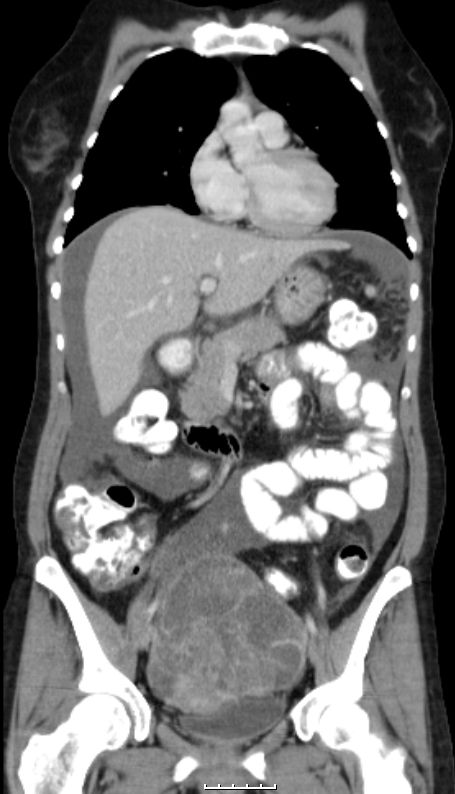

76-jährige Frau, die vor 13 Jahren ein Ovarial-Karzinom pT3b pNo Mo Lo Vo G2 hatte. Radikale OP, 6x Taxol - Carboplatin. Jetzt Lebermetastasen, RF linker Adnexbereich.